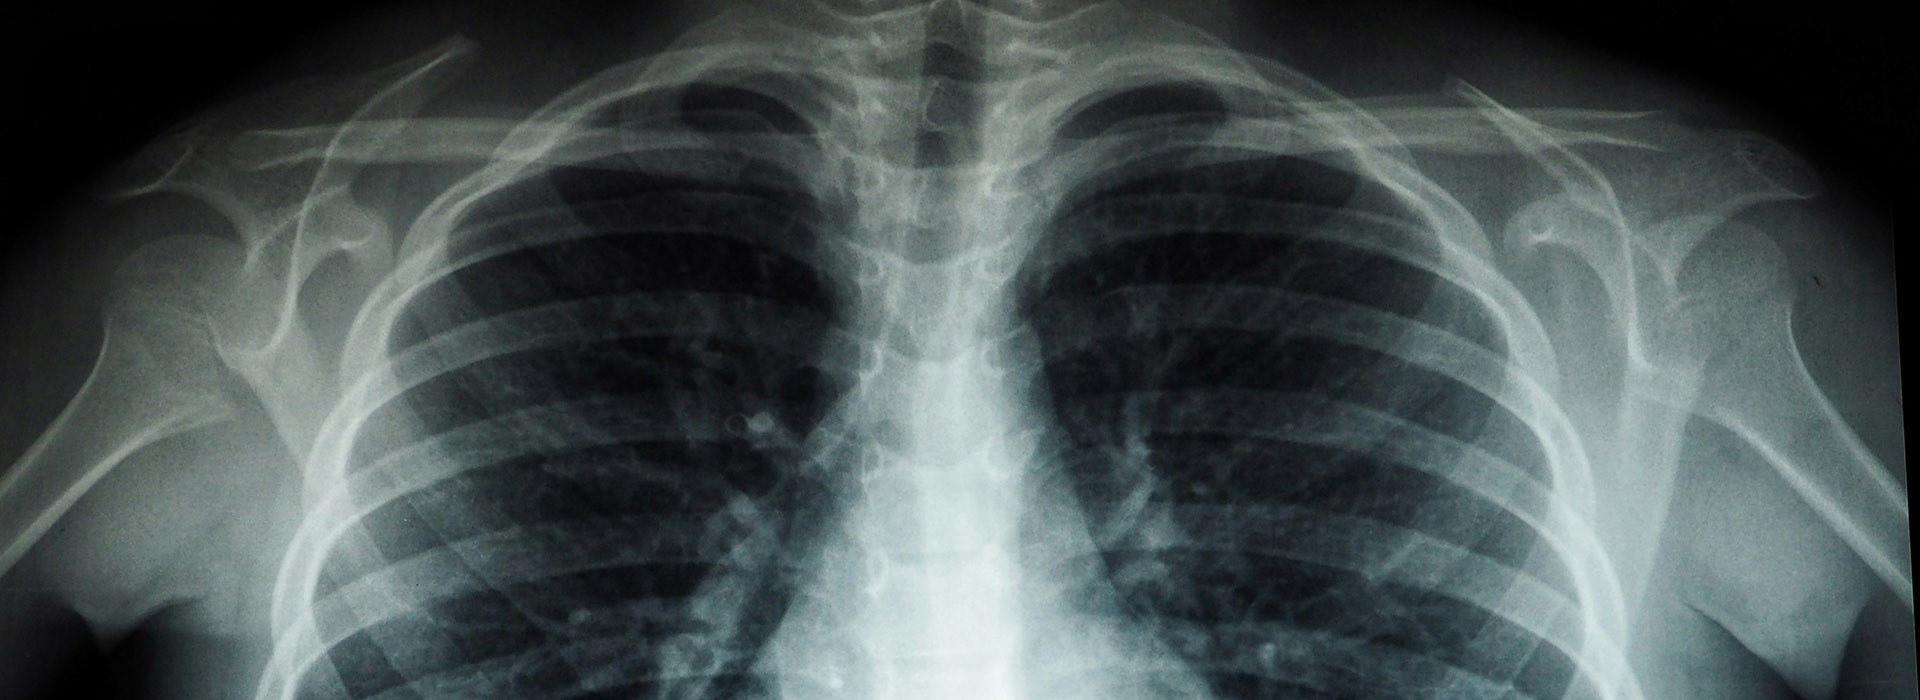

Image interpretation is a skill that is required by a range of healthcare professionals to enhance the service they provide, and the aim of this course is to enable practitioners to develop and/or improve their skills in interpretation of radiographic images of the chest.

Fundamentals of Radiographic Image Interpretation: Chest

- Evaluation of radiographic images to assess the presence of abnormal, normal, or variant appearances.